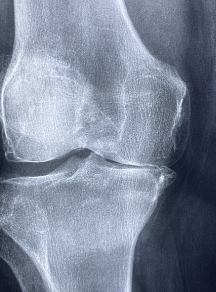

무릎 연골 손상 원인

무릎 연골 손상의 원인은 다양합니다. 가장 일반적인 원인은 다음과 같습니다.

- 외상적 원인: 스포츠에서의 부상이나 교통사고, 낙상 등으로 인해 무릎에 직접적인 충격을 받으면 연골에 손상이 생길 수 있습니다.

- 나이: 노화로 인해 연골의 탄성이 저하되고, 약해지면서 손상을 유발할 수 있습니다.

- 비만: 과체중이나 비만은 무릎 부하를 늘리고, 연골을 부담하게 하여 손상을 유발할 수 있습니다.

- 과도한 운동: 무릎을 과도하게 사용하거나, 잘못된 자세로 운동을 하는 경우에도 연골 손상을 유발할 수 있습니다.

- 무릎 관절염: 무릎 관절염은 연골을 파괴하고, 손상을 유발할 수 있습니다.

- 기타 질병: 척추측만증, 류마티스 관절염 등과 같은 다른 질병들도 연골 손상을 유발할 수 있습니다.

위와 같은 원인들이 무릎 연골 손상의 주요 원인입니다. 무릎 연골 손상은 조기에 진단하고 치료하지 않으면 심각한 후유증을 유발할 수 있으므로, 발생하면 적극적으로 치료가 필요합니다.